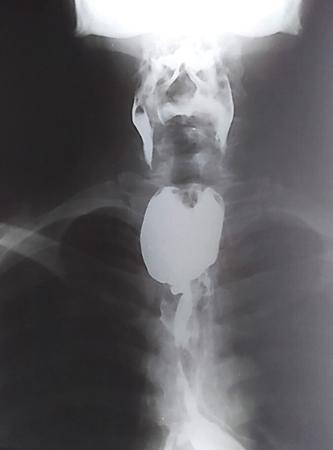

Clinical history

Fifty-year-old male with history of progressive dysphagia of six months’ duration associated with significant weight loss.

Radiological Technique: Barium swallow (barium oesophagography).

Observations

Barium oesophagogram showing a long segment of asymmetric mural thickening, ‘shouldering’ and mucosal irregularity with luminal narrowing (arrow) in the distal oesophagus and gastro-oesophageal junction, producing a ‘rat-tail’ appearance. There is upstream hold-up of contrast and dilatation of the oesophagus producing the ‘pseudoachalasia’ appearance.

Ancillary findings (of pseudoachalasia) – Decreased or absent peristalsis with luminal diameter usually <4 cm; length of narrowed segment is >3.5 cm.

Principal Diagnosis: Carcinoma distal oesophagus.

Differential Diagnosis: Achalasia cardia, stricture oesophagus, diffuse oesophageal spasm.